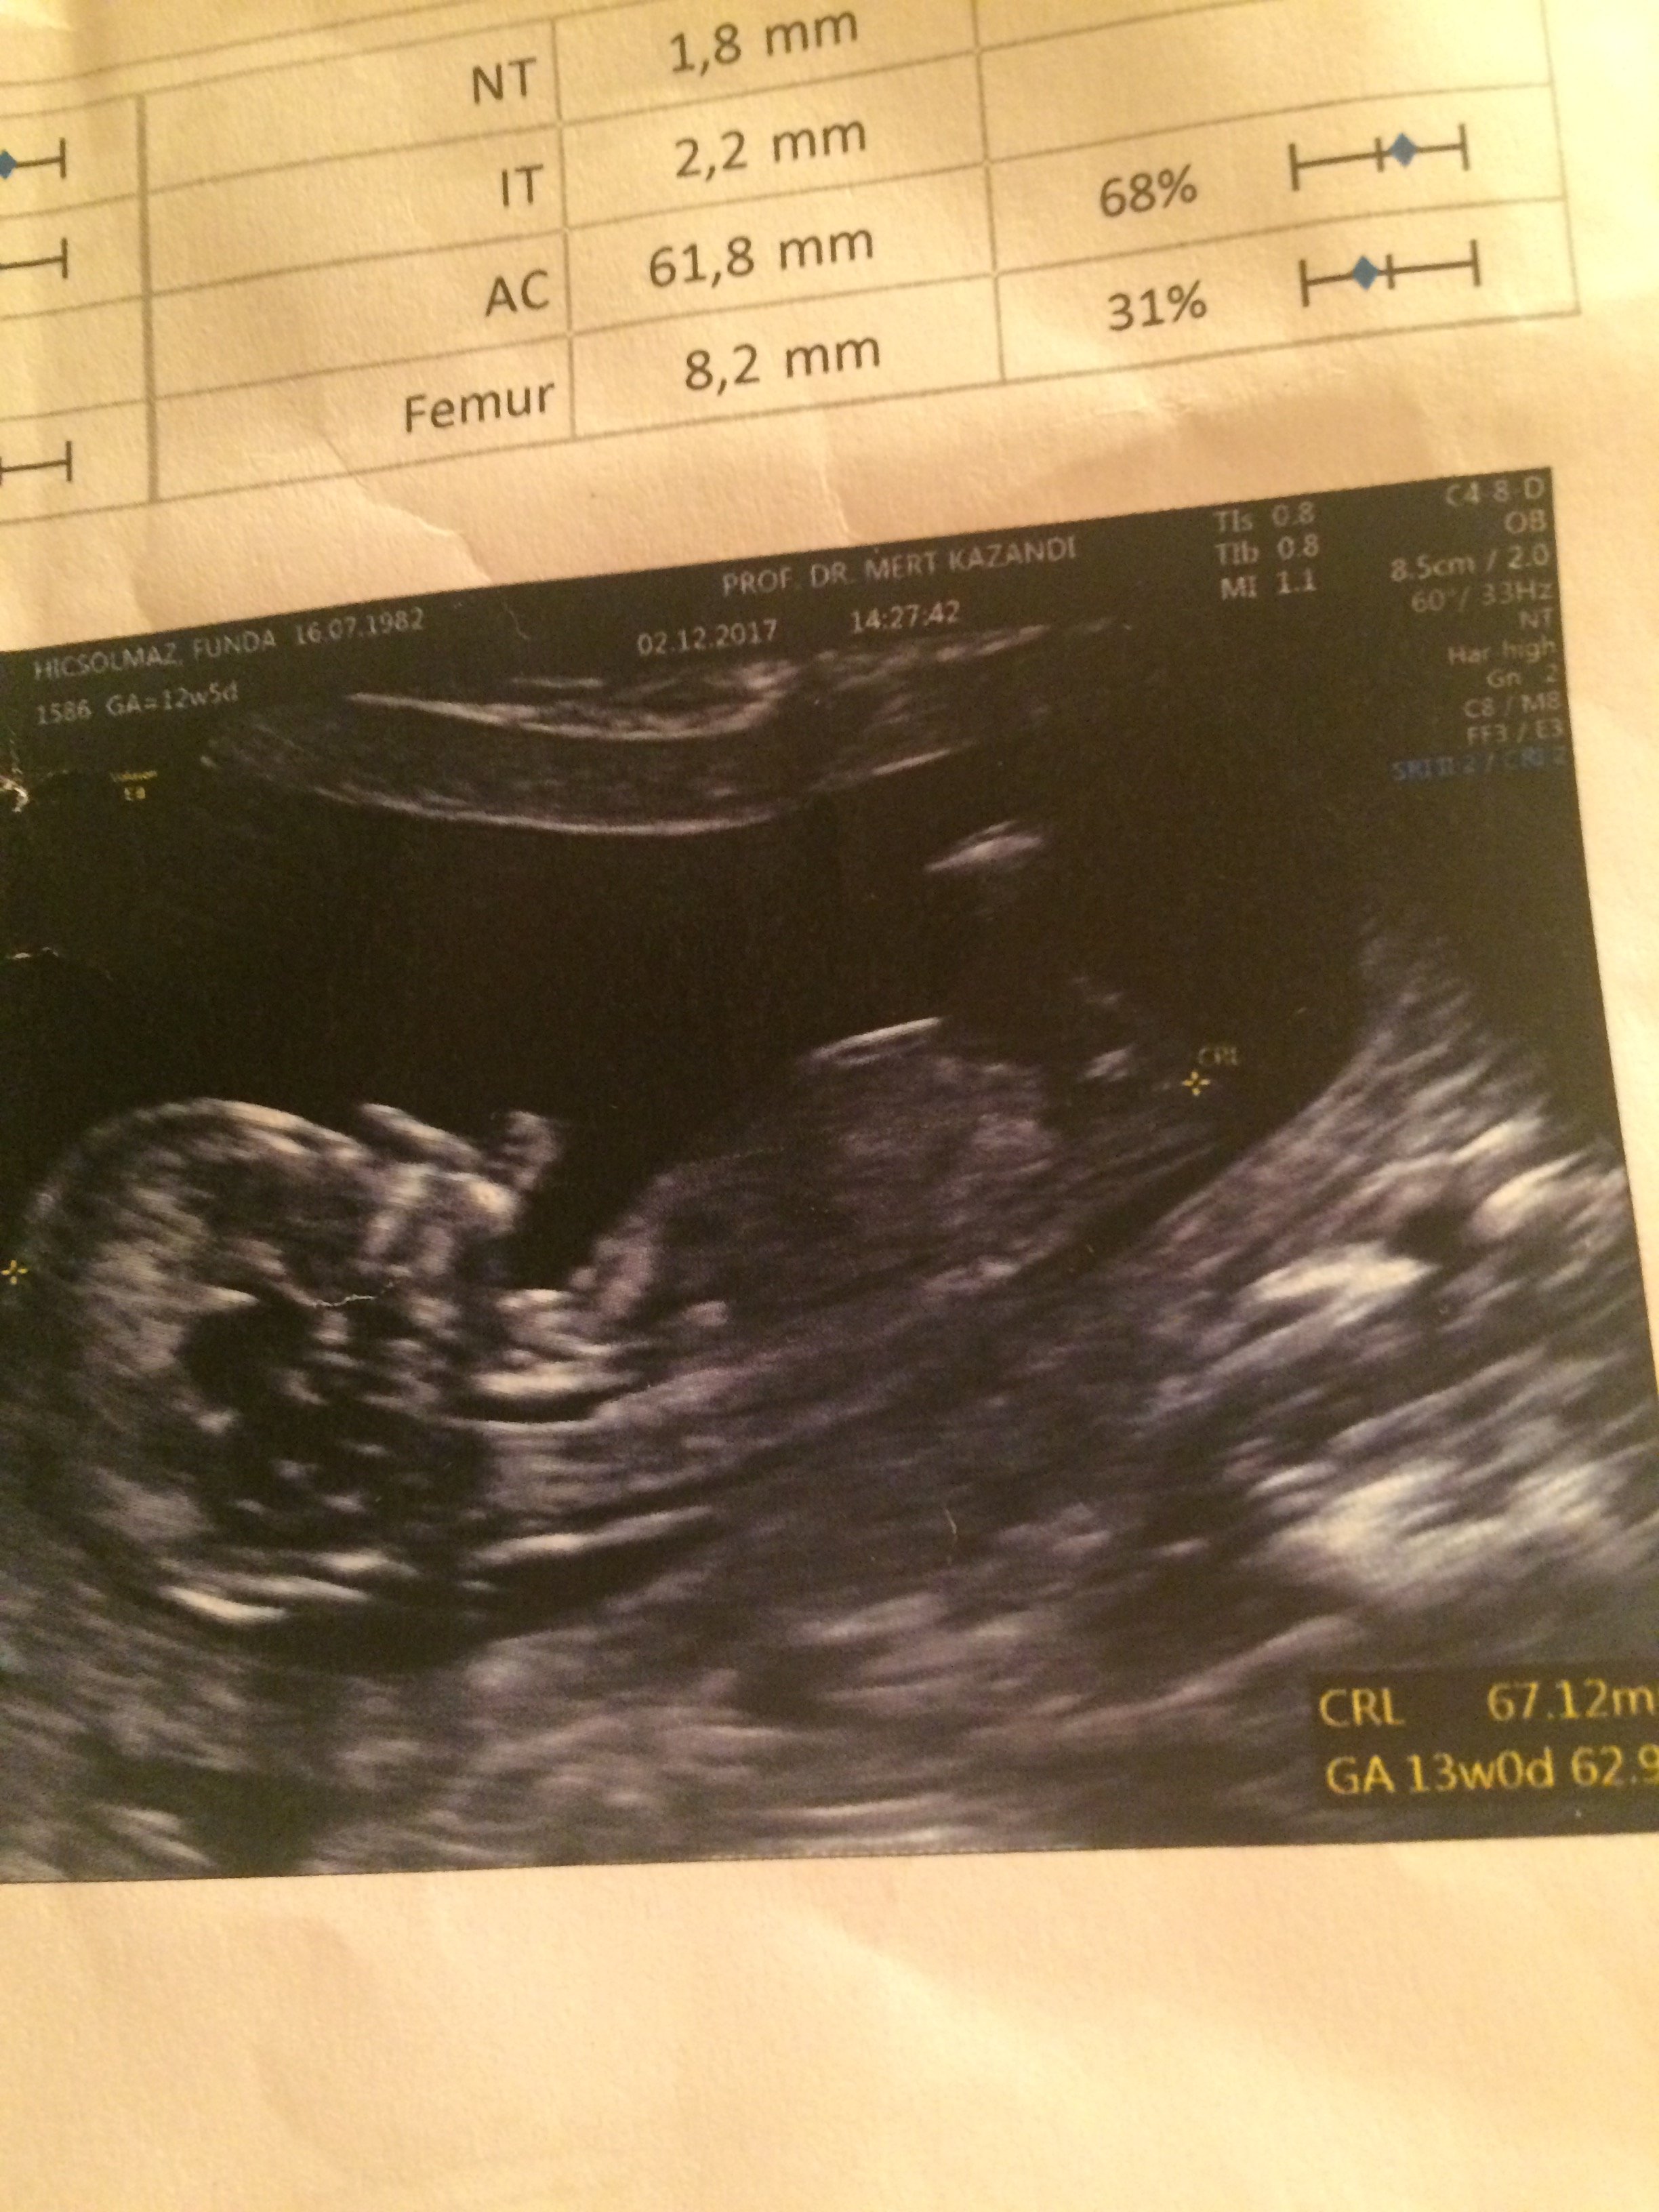

Merhaba 12 artı 6 haftalık gebelik ,tahmin alabilirmiyim acaba

Merhaba, nub çıkıntısı tamamiyle görülmüyor. Emin olmamakla birlikte bebeğinizin cinsiyetinin kız olduğu kanısındayım. Bu haftalarda zaten cinsiyetin teşhisi kesin olarak saptanmaz . 20 hafta ve sonrası bebeğin cinsiyeti net olarak anlaşılabilir. Bu uyarımızı da yapalım.